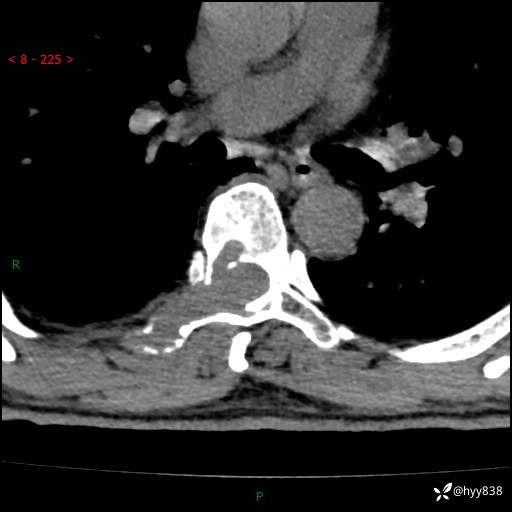

辅助检查:CT MRI

胸椎CT平扫(骨窗+软组织窗)